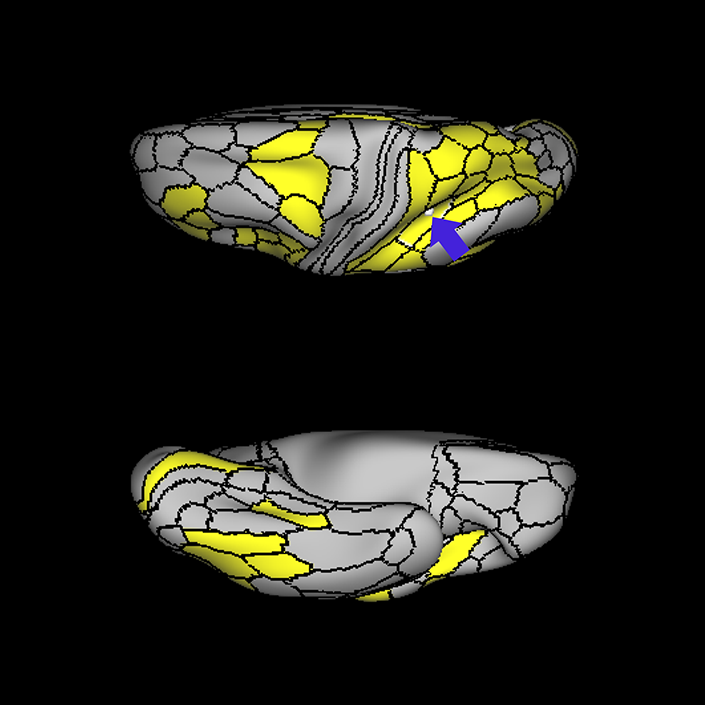

ᐅ SummaryArea 45: part of the inferior frontal gyrus of the lateral frontal lobe. In addition to its known association with Broca's area, is sometimes represented as part of Broca's complex ᐅ Where is it?Area 45 is the lateral surface of pars triangularis of the IFG. ᐅ What are its borders?Area 45 borders area 47L anteriorly and area 44 posteriorly. Its superior edge borders area p47r, IFSa, and IFSp. Its opercular surface is conveniently named FOP5 ᐅ What are its functional connections?Area 45 demonstrates functional connectivity to areas SFL, IFSp, 44, a47r, 47s, 47L, 9a, 9p, 9m, 8AV, and 8BL in the dorsolateral frontal lobe, area 8BM in the medial frontal lobe, area 55b in the premotor areas, areas FOP5, and PSL in the insula-opercular region, areas TGd, TGv, TE1a, STSva, STSdp and STSvp in the temporal lobe, area PGi in the inferior parietal lobe, and area 31pd in the medial parietal lobe. ᐅ What are its white matter connections?Area 45 is structurally connected to the arcuate/SLF and IFOF. However, arcuate/SLF connections are not consistent across individuals. Connections with the arcuate/SLF project posteriorly and wrap around the Sylvian fissure to the middle temporal gyrus to end at TE1p. There are also projections from the arcuate/SLF before it terminates to parcellations A4 and PBelt. IFOF connections travel from 45 through the extreme/external capsule and continue posteriorly through the temporal lobe to end at occipital lobe parcellations V1, V2, V3 and V4. Local short association bundles connect with 44 and FOP4. ᐅ What is known about its function?Area 45, in addition to its known association with Broca's area, is sometimes represented as part of "Broca's complex", including Brodmann Areas 45, 46, 47 and the mesial supplementary motor area of 6, which contribute to a frontal-subcortical circuit. |

A: lateral-medial

B: anterior-posterior

C: superior-inferior

DTI image |